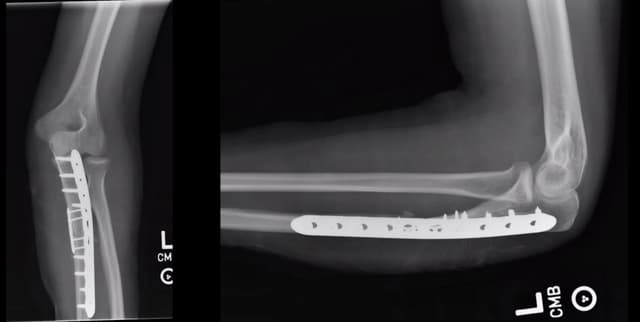

Pre-op

Post-op